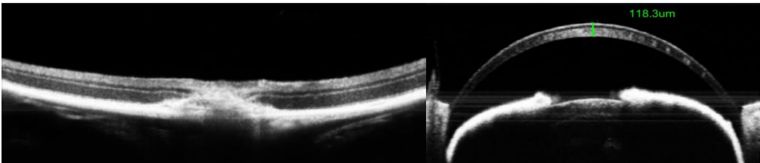

视网膜、角膜OCT断层图---可定量分析

可视化视网膜下腔注射隆起高度定量化,对应药物剂量对视网膜影响研究

基因治疗、干细胞治疗视网膜下腔注射---排除视网膜下腔物理损伤得影响